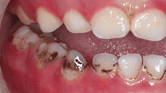

I was horrified one day to find black stains all over my then 2 yr old’s teeth which I couldn’t remove with a toothbrush. I thought they were cavities and brought him to the pediatric dentist right away. Surprisingly, the dentist didn’t know what caused the stains or what the black stains were even called. After ruling out foods, iron intake and poor brushing habits, he suspected something had changed the flora in my child’s mouth. Perhaps the Xoponex (an asthma medication) that he had taken for a cold a few months earlier. A few other pediatric patients also had similar black stains and those stains were not cavities and on the contrary, often associated with a low incidence of cavities.

I discovered that the black stains are caused by chromogenic bacteria and they feed off of the plaque on the teeth. The fact that our kids were not consumers of tea, coffee, iron supplements, dried fruit and other stain-creating foods leads us to believe that their stains were not caused by these culprits as commonly suggested by dentists. Our pediatric dentist said anecdotally that the black stains seem to occur more frequently with the Asian and Hispanic population. It varies in degree of severity. I see many posts where adults complain of having these stains, and not being able to keep the stains at bay (frequent dental visits not enough, regular brushing, etc). I also read about one frustrated woman whose children had lots of stains recurring as quickly as the day after their dental visit. Because it’s bacteria, it needs plaque to grow so it tends to appear along the gumline and in grooves and spots where it is difficult to brush well or where food sugars tend to linger between brushing sessions.